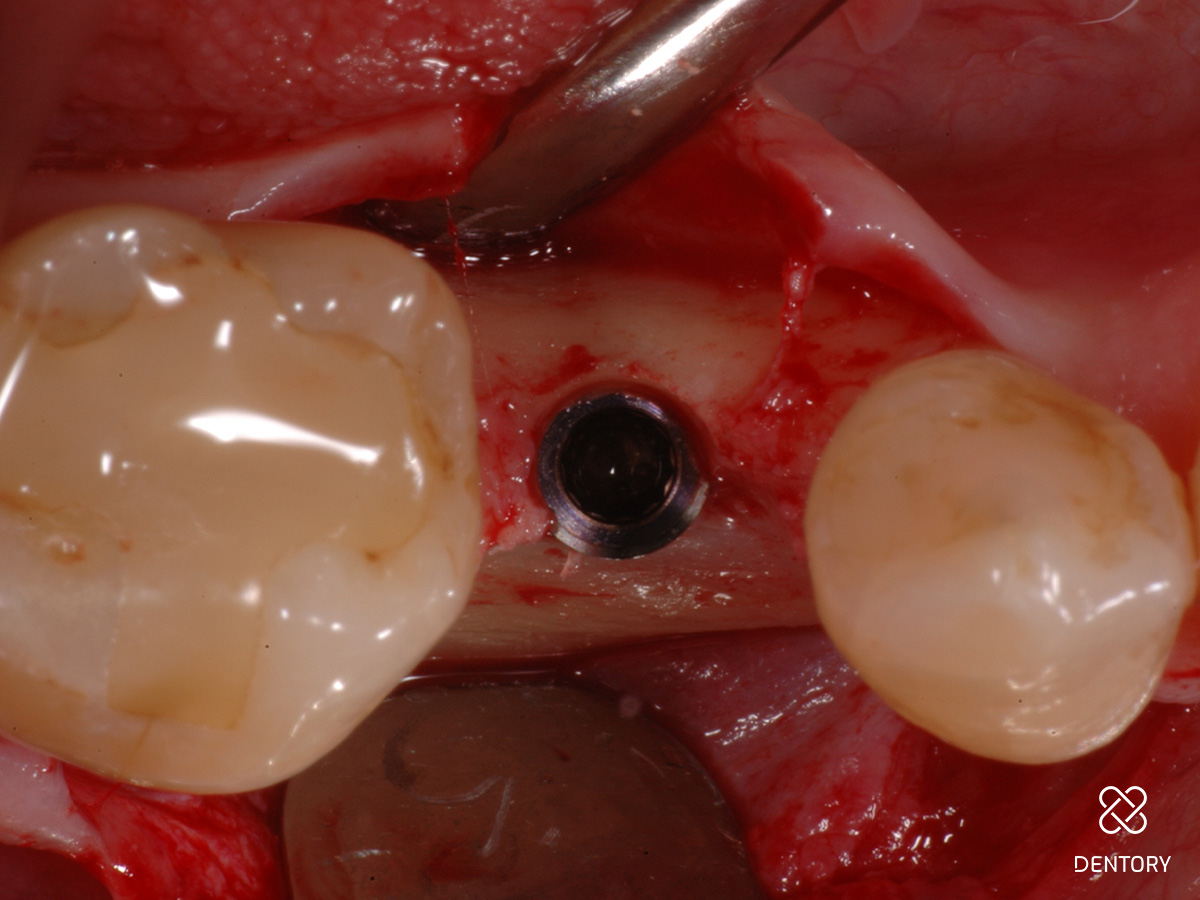

Abbildung 2

Simultane Implantation und GBR: Darstellung des späteren Implantatlagers nach Elevation eines Mukoperiostlappens; es zeigt sich ein horizontal ungenügendes Knochenangebot.